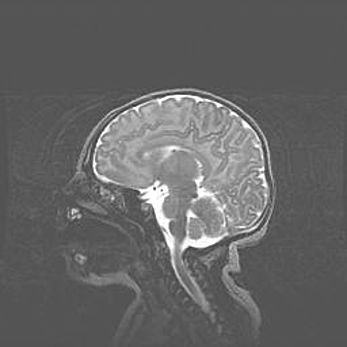

Церебральная ишемия II.

Возраст: 5 дней

Вес: 3400 г

Пол: женский

Окружность головы: 35 см

Срок гестации: 39 недель

Церебральная ишемия – это заболевание, характеризующееся недостаточностью (гипоксией) либо полным прекращением (аноксией) снабжения мозга кислородом по причине закупорки одного или нескольких сосудов. Это приводит к  что метаболическим расстройствам различной степени тяжести в тканях головного мозга, развитию коагуляционных некрозов и гибели нейронов.